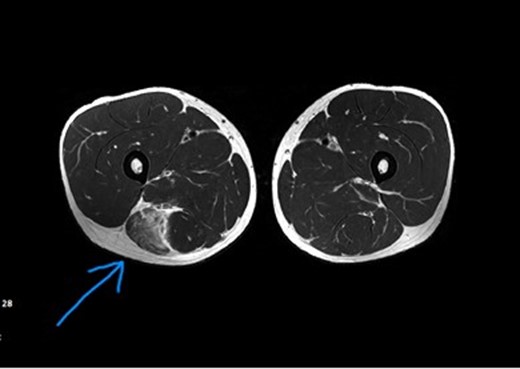

Η έγκαιρη διάγνωση της θλάσης πραγματοποιείται από τον Ορθοπεδικό χειρουργό με εξειδίκευση στην αντιμετώπιση αθλητικών κακώσεων στο ειδικά εξοπλισμένο ιατρείο με συνδυασμό λεπτομερούς κλινικής εξέτασης και υπερηχογραφικού ελέγχου των τραυματισμένων μυών. Σε ορισμένες περιπτώσεις μπορεί να χρειαστεί ο απεικονιστικός έλεγχος με μαγνητική τομογραφία.

Η θλάση ορίζεται ως η μερική ή ολική ρήξη των μυϊκών ινών ή ακόμα και ολόκληρου του οπίσθιου μηριαίου μυός. Μπορεί να επηρεάσει έναν ή και παραπάνω από τους οπίσθιους μύες του μηρού και ανάλογα με τη βαρύτητα οι θλάσεις χωρίζονται σε 1ου, 2ου και 3ου βαθμού.